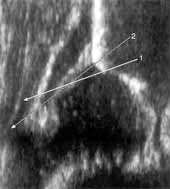

Вторая по частоте ошибка — ошибочное определение костного выступа. По определению Графа костный выступ (эркер) — это переход от вогнутости к выпуклости (от конкавитета к конвекситету) и начинать искать его надо от нижнего края подвздошной кости в краниальном направлении. При поисках в обратную сторону эркер ошибочно определяется в большинстве случаев выше (Рис. 8). Встречается также ошибочное определение нижнего края подвздошной кости, особенно на некачественных сонограммах. Нижний край подвздошной кости должен быть представлен в виде четкой структуры, разграниченной с другими анатомическими образованиями суставной впадины (Рис. 9).

Вторая по частоте ошибка — ошибочное определение костного выступа. По определению

Графа костный выступ (эркер) — это переход от вогнутости к выпуклости (от конкавитета

к конвекситету) и начинать искать его надо от нижнего края подвздошной кости

в краниальном направлении. При поисках в обратную сторону эркер ошибочно определяется

в большинстве случаев выше (Рис. 8). Встречается также ошибочное определение